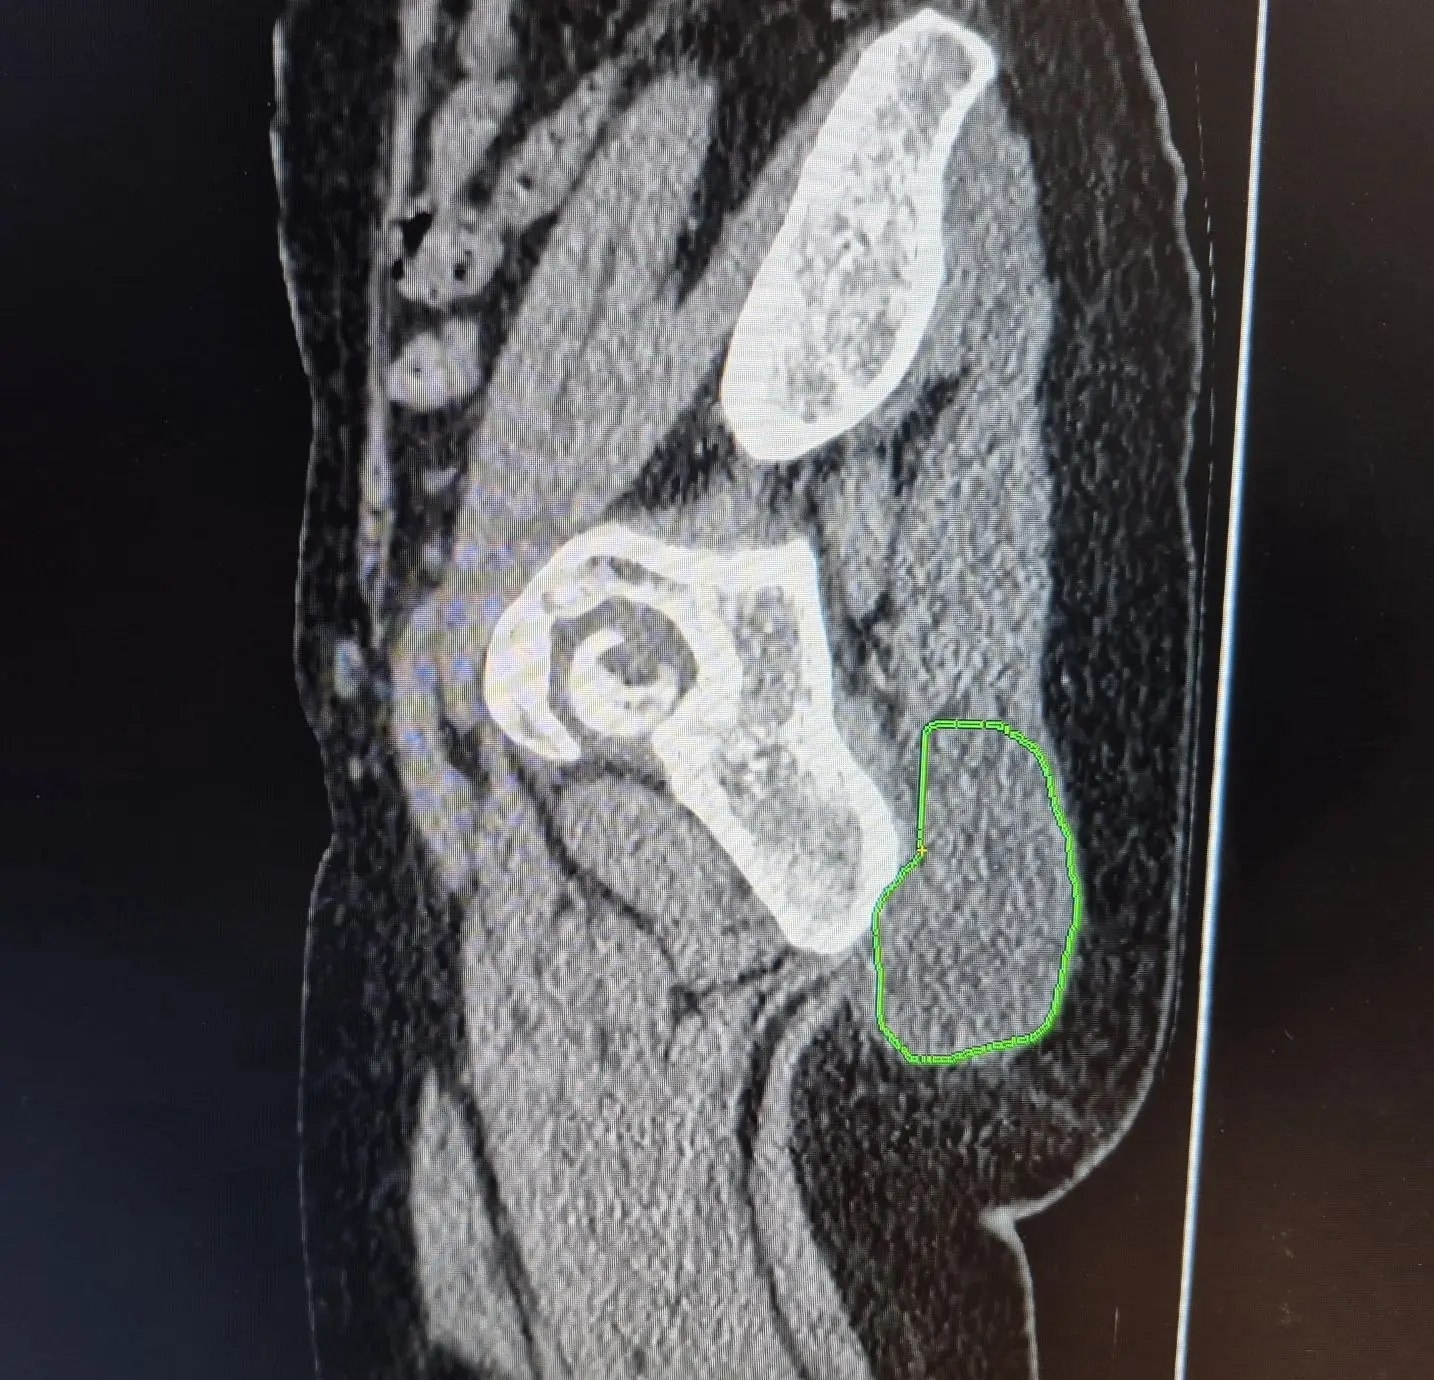

Результат оказался пугающим: после активного механического воздействия опухоль начала стремительно увеличиваться и достигла 10 сантиметров. Обследование в БГКБ (УЗИ, компьютерная томография и биопсия) показало, что «жировик» оказался злокачественным новообразованием, выросшим из жировой ткани.